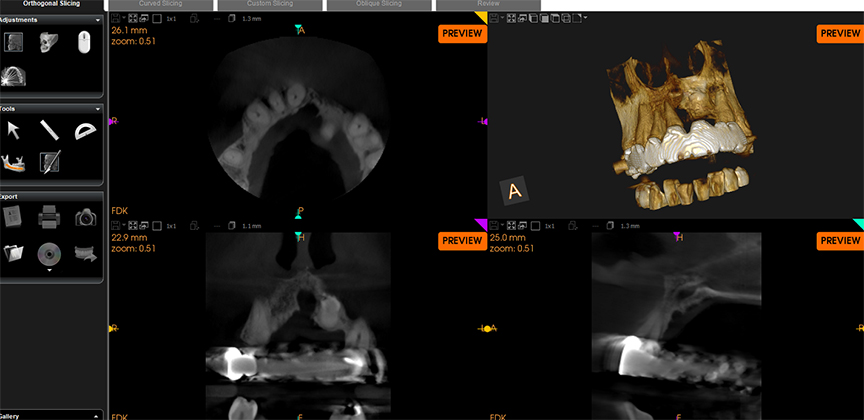

Cone Beam Computer Tomography (CBCT) scanning is the dental equivalent of a medical CT scan. The image machine rotates around the patient’s head, collecting hundreds of images in less than a minute. From these images, it can create a highly detailed digital 3D image that will allow endodontists to view your teeth and surrounding tissues from all different angles.

With just one CBCT scan, your Endodontic needs can be assessed, diagnosed, and organized into a treatment plan. It provides an avenue to an incredibly high level of dental care.